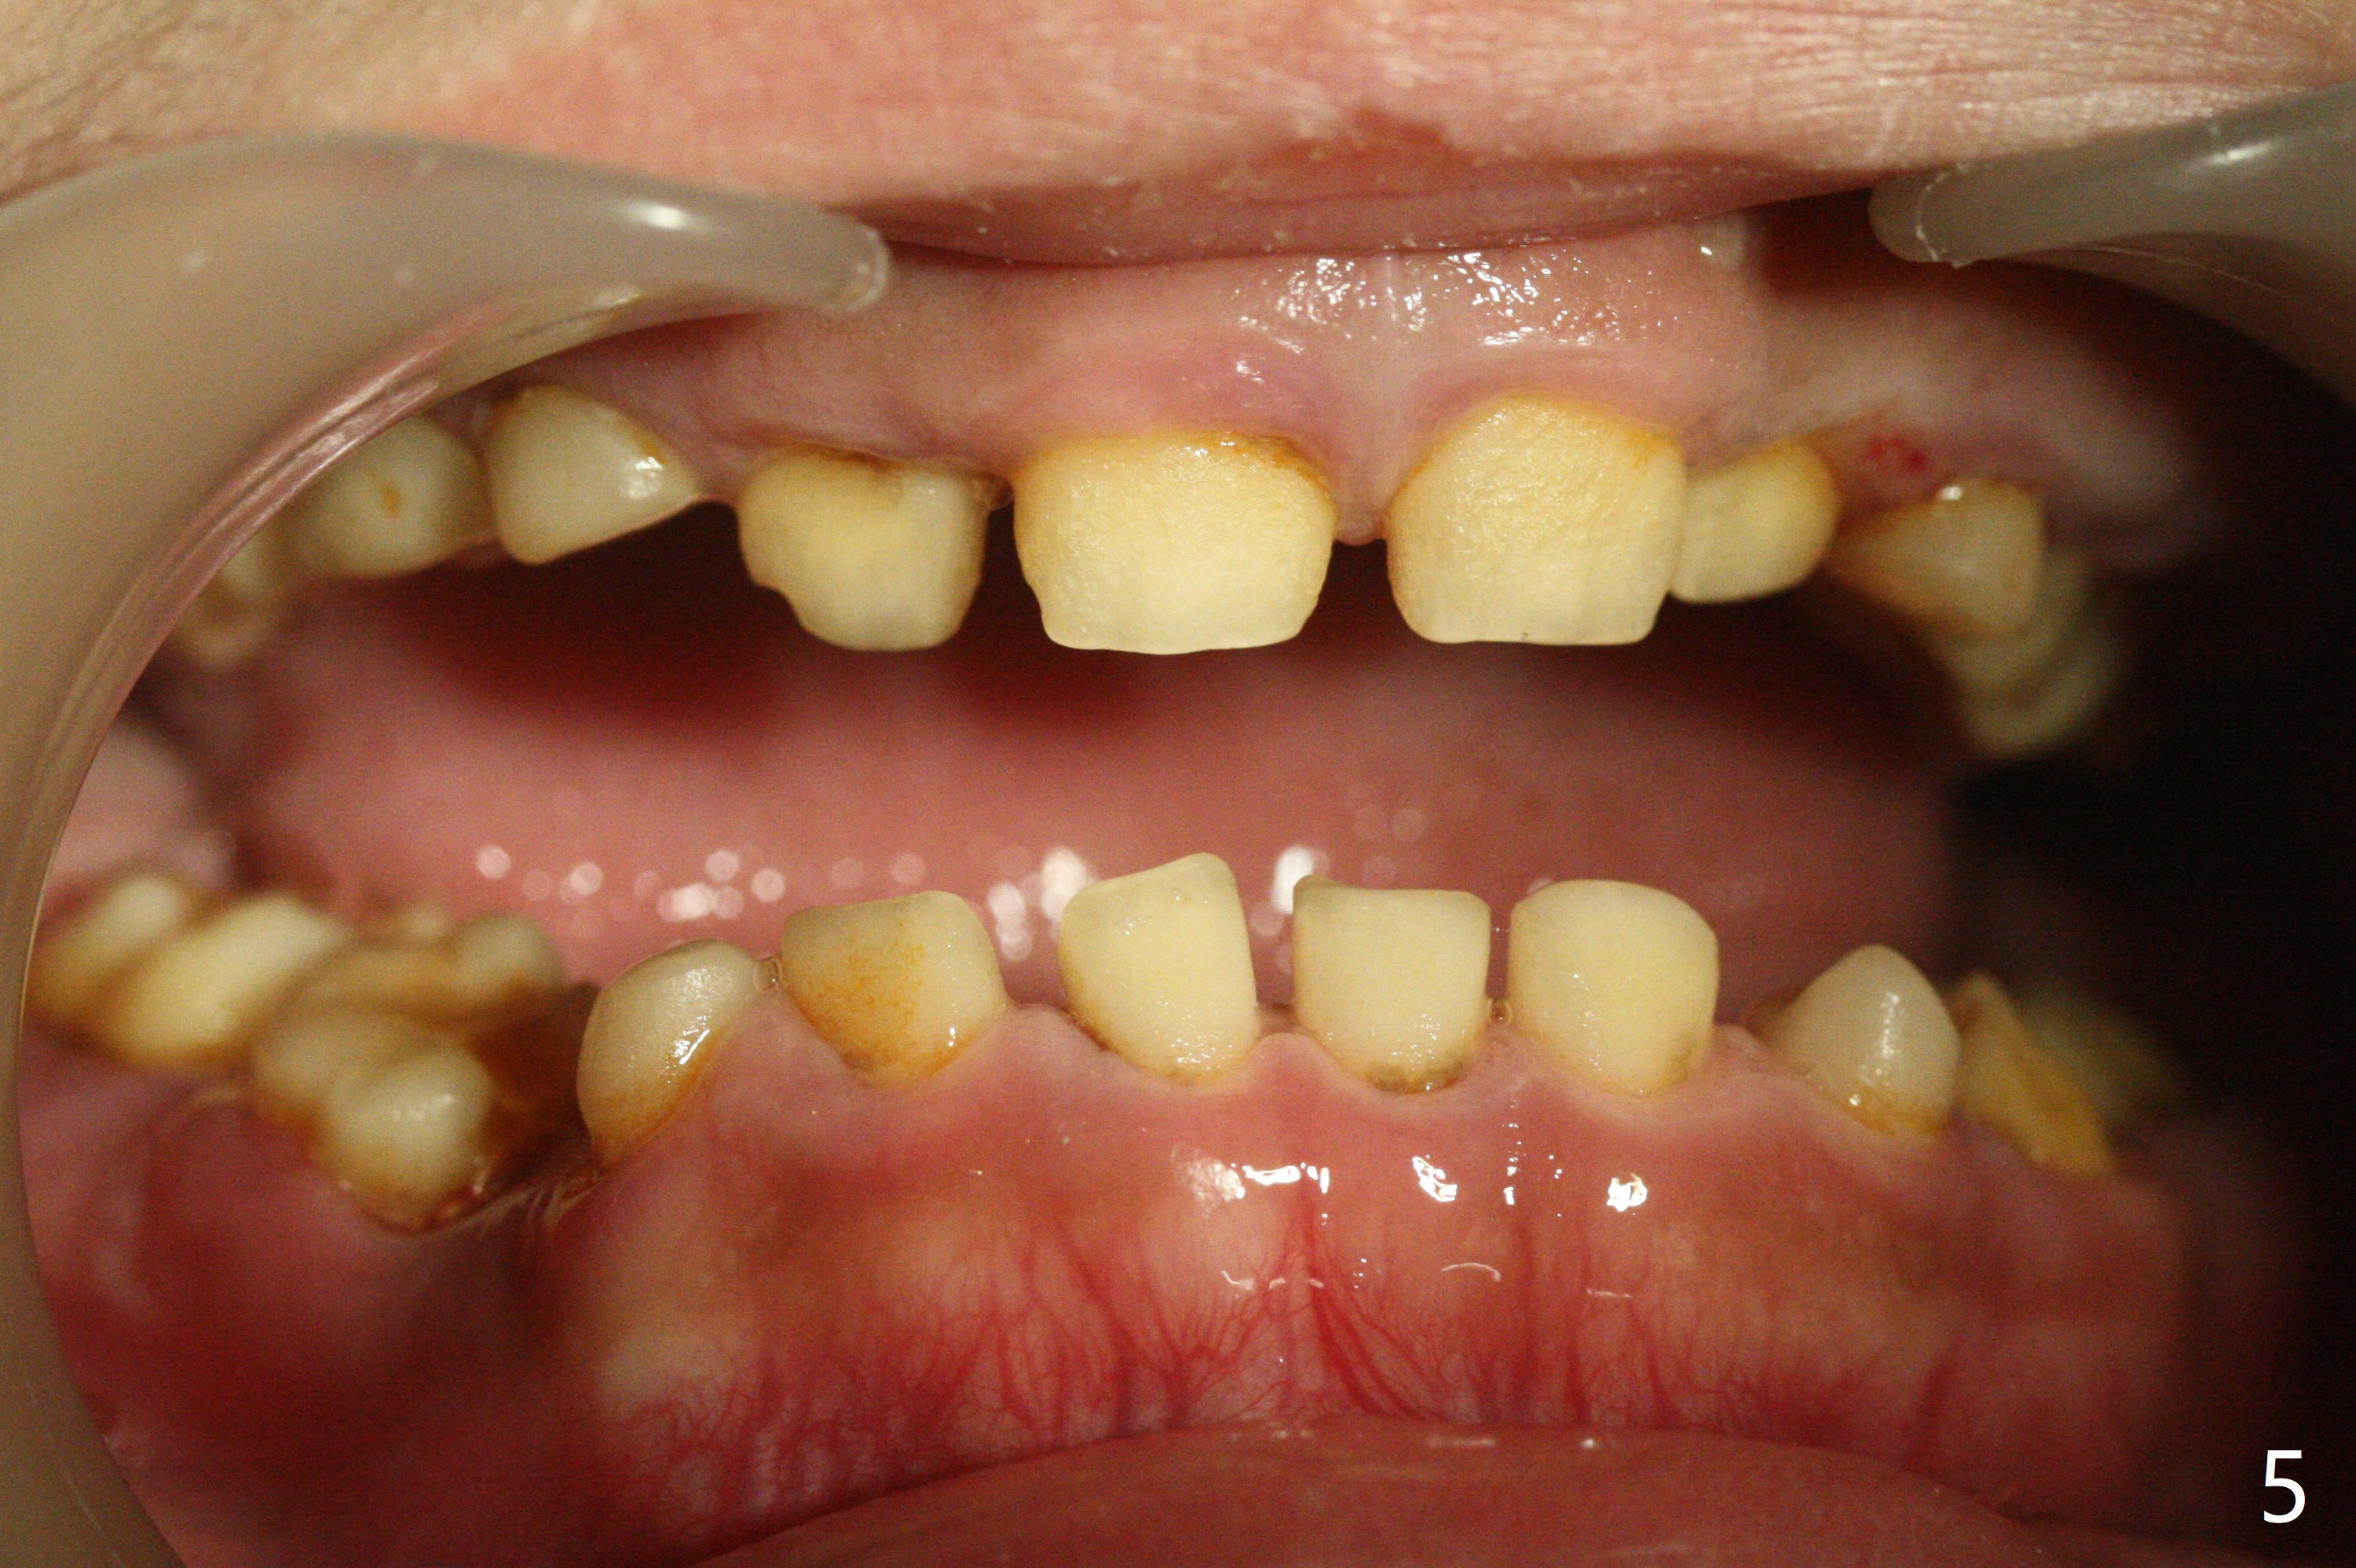

13岁男孩,每颗乳恒牙交换时乳牙都需要拔除,萌出的恒牙个子小,侧切牙反合(图二,五),对冷热敏感,不爱刷牙,口腔卫生欠佳(图三:13(结石)),父母要求诊治。今天在局麻下,左上洁治,没有局麻区域无法洁治,敏感,并且拔除H-J。S下沉,5,28埋伏(图七),其余乳磨牙都有龋齿。如何治疗?是釉质发育不全?暴露5,28前将拍摄CT。